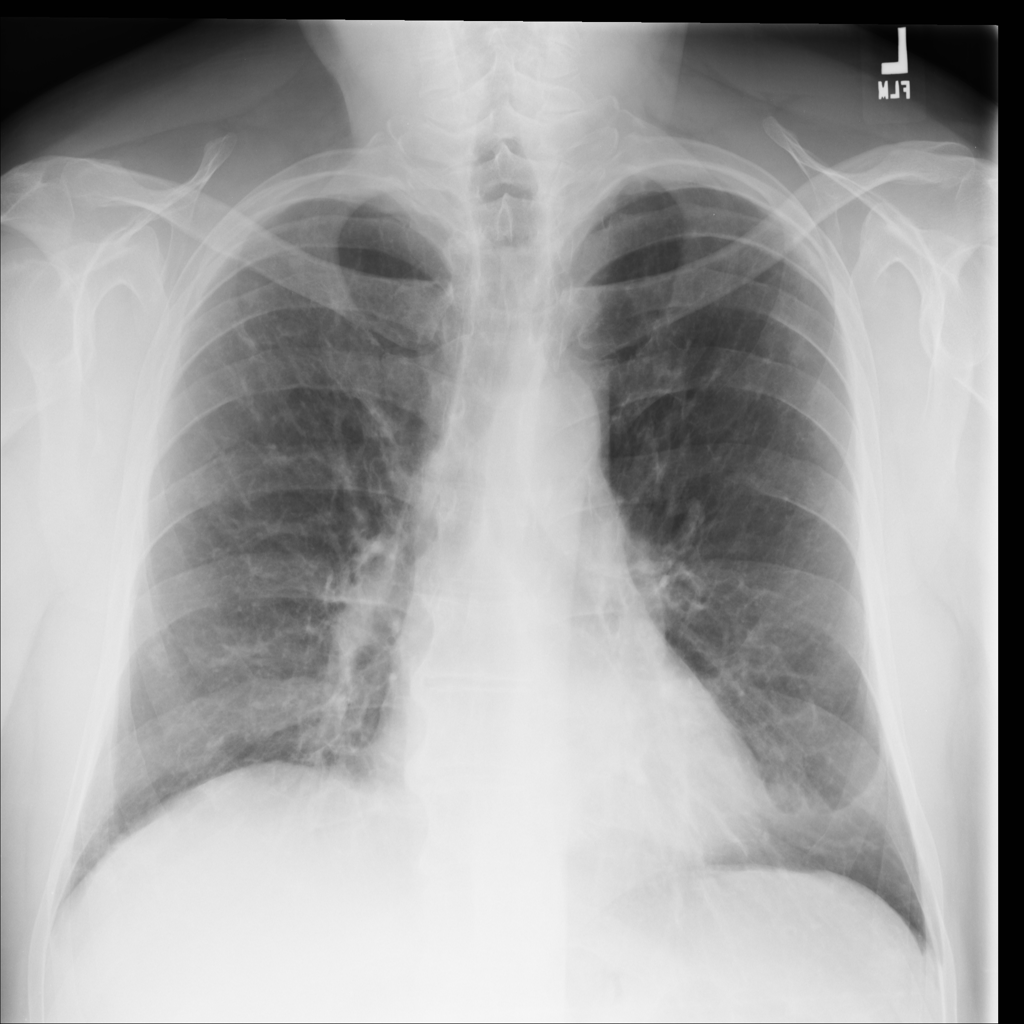

PAT-E066 · IMG-010Fibrosis

PAT-E066 · IMG-010

PA